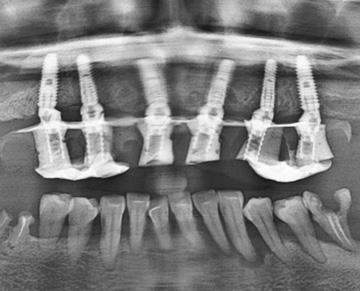

※在舒眠麻醉下完成六顆植體植入

在專業評估後,我們決定採用 All-on-6全口重建,為她開啟新人生

電腦設計+斷層掃描,植體定位更安心